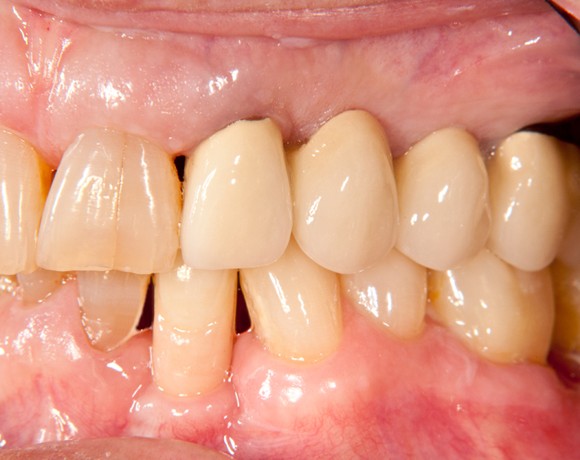

Bei dieser Patientin mussten die Zähne 22,26 und 27 aus parodontalen Gründen entfernt werden. Nach Extraktion der Zähne 22 und 26 wurden sofort in die Extraktionsalveolen die Implantate gesetzt. Zahn 27 war bereits sechs Monate zuvor extrahiert worden und die Knochenwunde gut ausgeheilt. Das geringe Knochenangebot wurde mit einem internen Sinuslift ausgeglichen. Im Bereich des Zahnes 23 wurde noch ein weiteres Implantat gesetzt. Da der Zahn 12 nicht angelegt und die Symetrie auf dieser Seite gestört war, wurden die Zähne 11 und 13 mit Teilkronen versorgt, um die Lücken zu schließen der Zahn 13 zu 12 umgebaut.